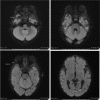

Case presentation: We report the case of a Salmonella meningitis in a Belgian six-month old male infant. The first clinical examination was reassuring, but after a few hours, his general state deteriorated. A blood test and a lumbar puncture were therefore performed. The cerebrospinal fluid analysis was compatible with a bacterial meningitis which was later identified by the NRC (National Reference Center) as Salmonella enterica serovar Durban.